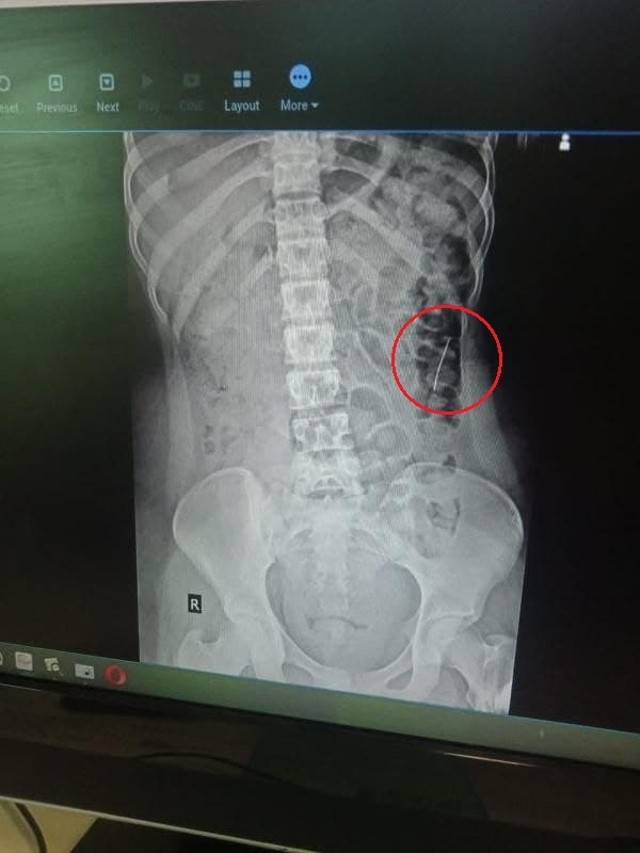

Batam, Batamnews - Dua buah jarum pentul tertelan oleh Fitri Ramadani (16), gadis asal Kecamatan Moro Kabupaten Karimun. Akibat kejadian yang dialaminya, Kamis (18/11/2021) lalu itu, Fitri pun menderita sakit di bagian perut, sesak nafas hingga muntah berdarah.

Ia sempat dibawa Puskesmas Moro, dirujuk ke RSUD Karimun hingga akhirnya dibawa ke RS Awal Bros Kota Batam. Dua jarum itu tampak jelas dalam hasil rontgent yang dilakukan pihak rumah sakit.

Dalam pengobatan di RSAB, satu jarum keluar bersama buang air besar. Hal ini membuat orangtua Fitri, Mariana sedikit lega. Kendati saat BAB ia mengalami pendarahan.

“Sampai di Batam di rontgent ulang, alhamdulillah jarum tinggal satu. Pas di BAB berdarah mungkin itu keluar dengan sendirinya,” ujar Mariana, Minggu (28/11/2021).

Selain jarum yang tinggal satu, Mariana juga menyebutkan ada kabar baik lainnya dari yang disampaikan dokter kepadanya, yaitu posisi jarum yang masih tertinggal di dalam sudah berada di posisi usus besar pembuangan.